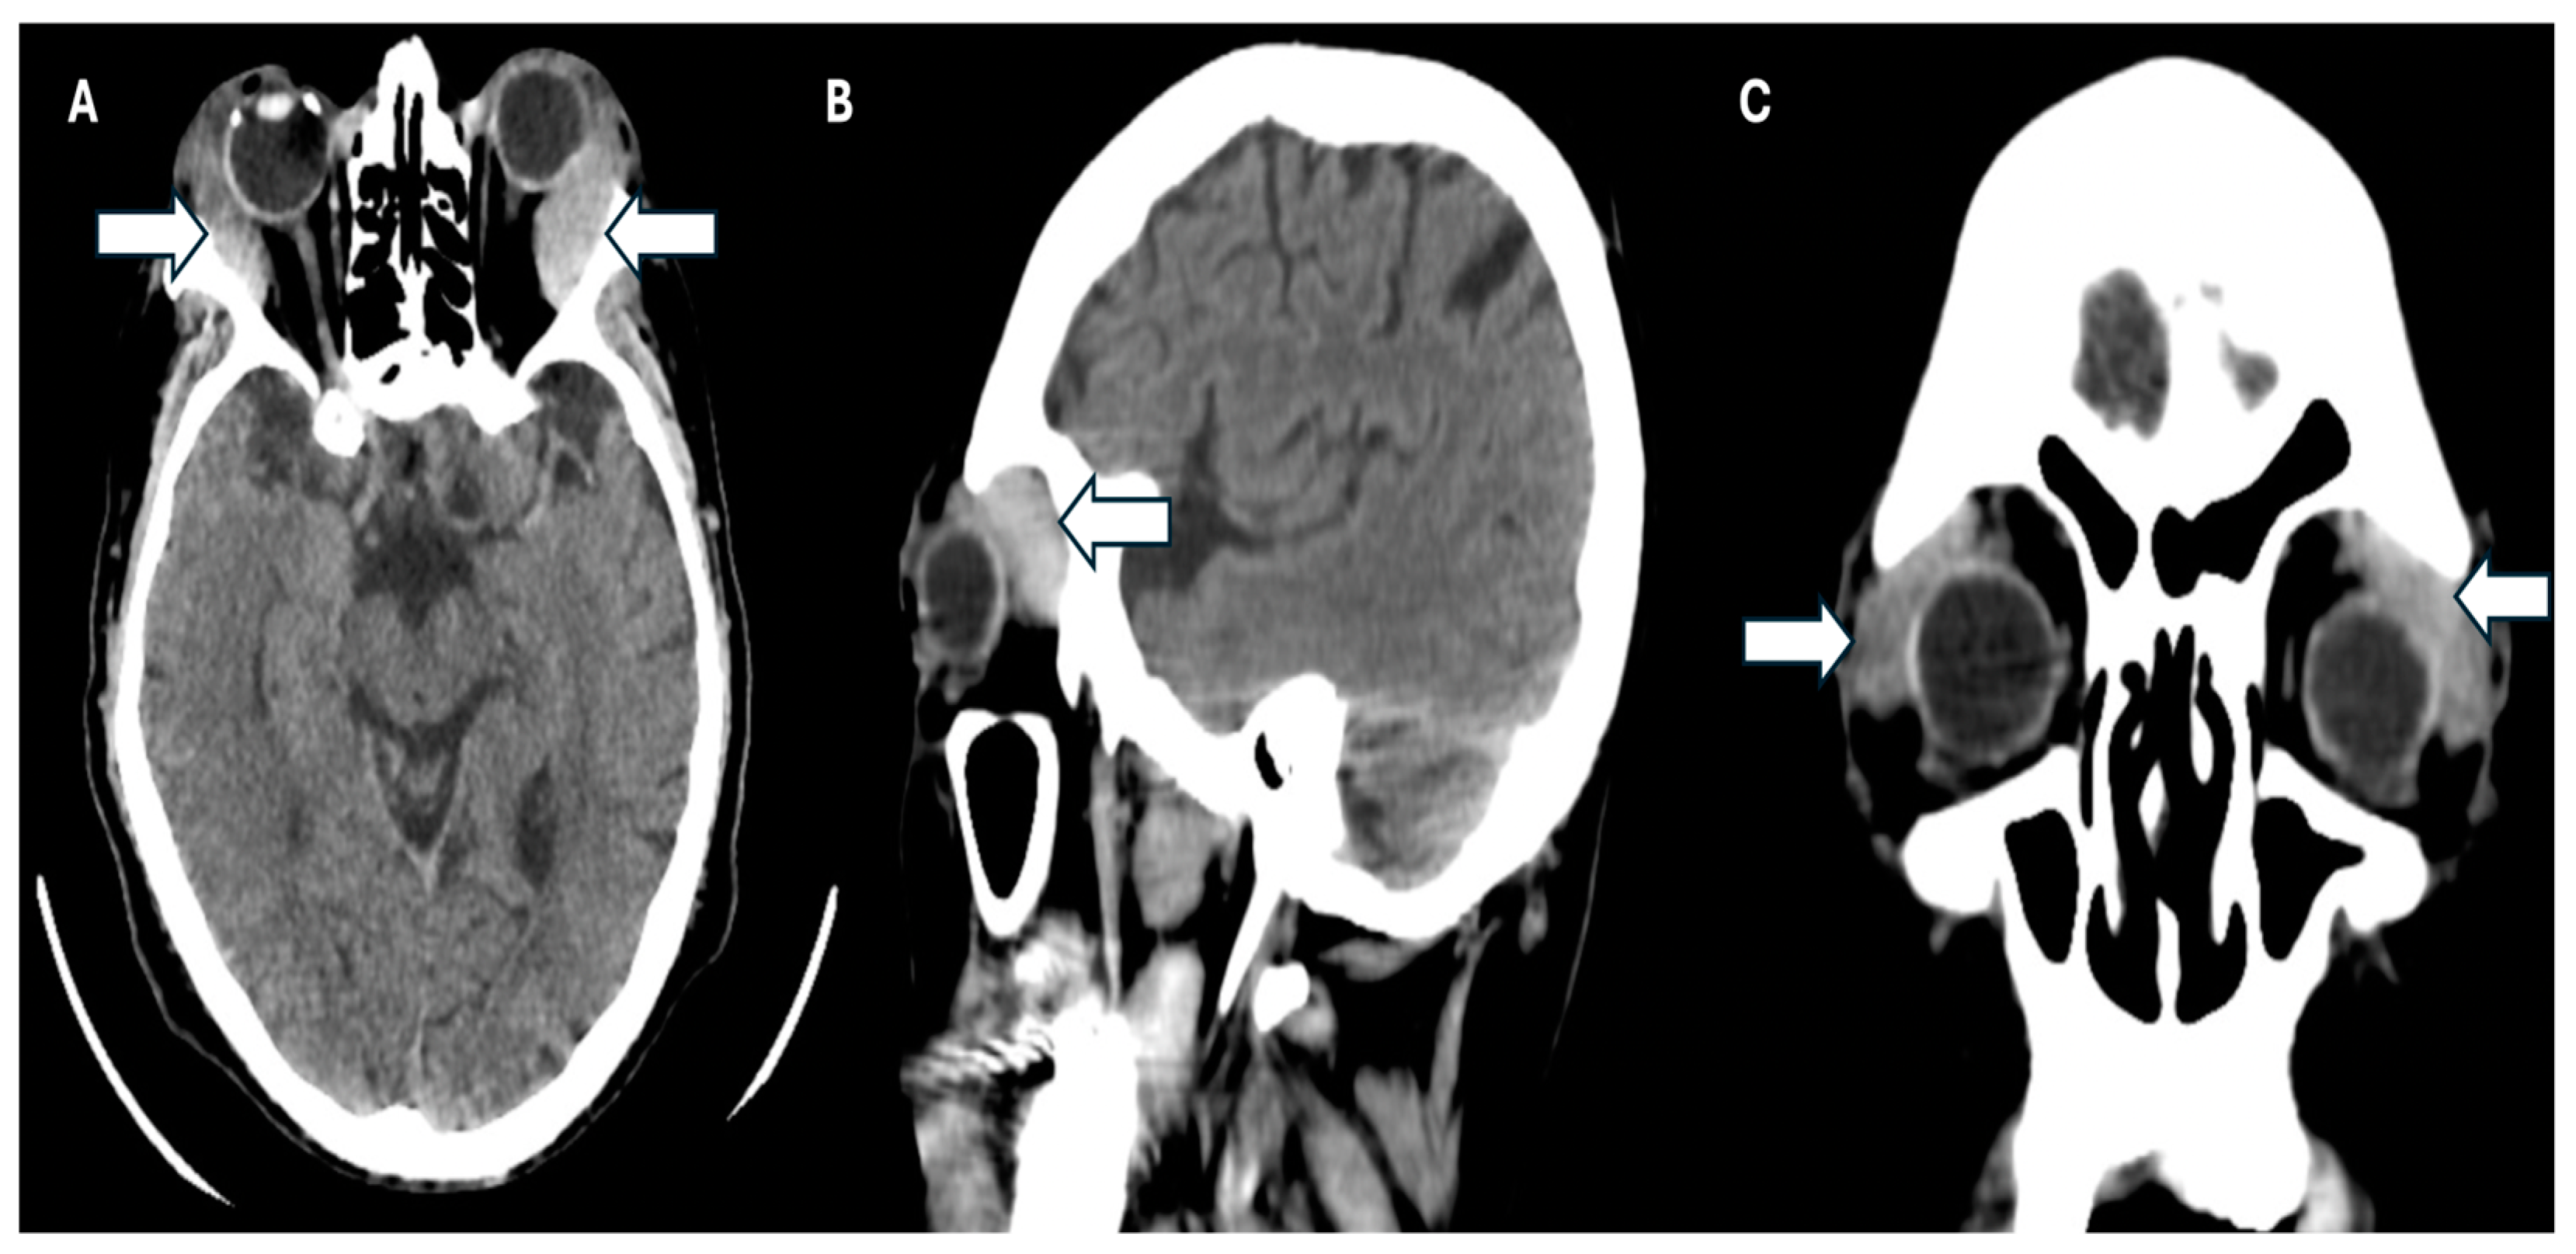

Simultaneously, a simple phase cranial computed axial tomography (CT) scan was requested to continue the approach. This revealed the presence of heterogeneous masses in the upper temporal sector of both orbits at the level of the lacrimal glands and infiltration of the adjacent orbital tissue, causing bilateral proptosis. Additionally, there was evidence of bilateral maxillary sinusitis, with no indication of periorbital cellulitis (Figure 3A–C).

Figure 3.

CT scan of the patient. (A) Axial plane, (B) sagittal, and (C) coronal plane where the arrows show infiltration of the adjacent orbital tissue, causing the patient’s bilateral proptosis.